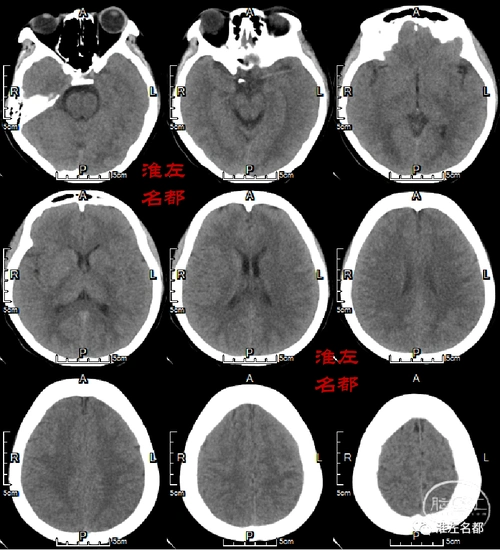

颅脑ct平扫:左侧基底节区可见少许低密度影,aspect-9.